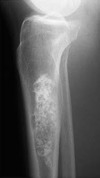

A

Infarto óseo